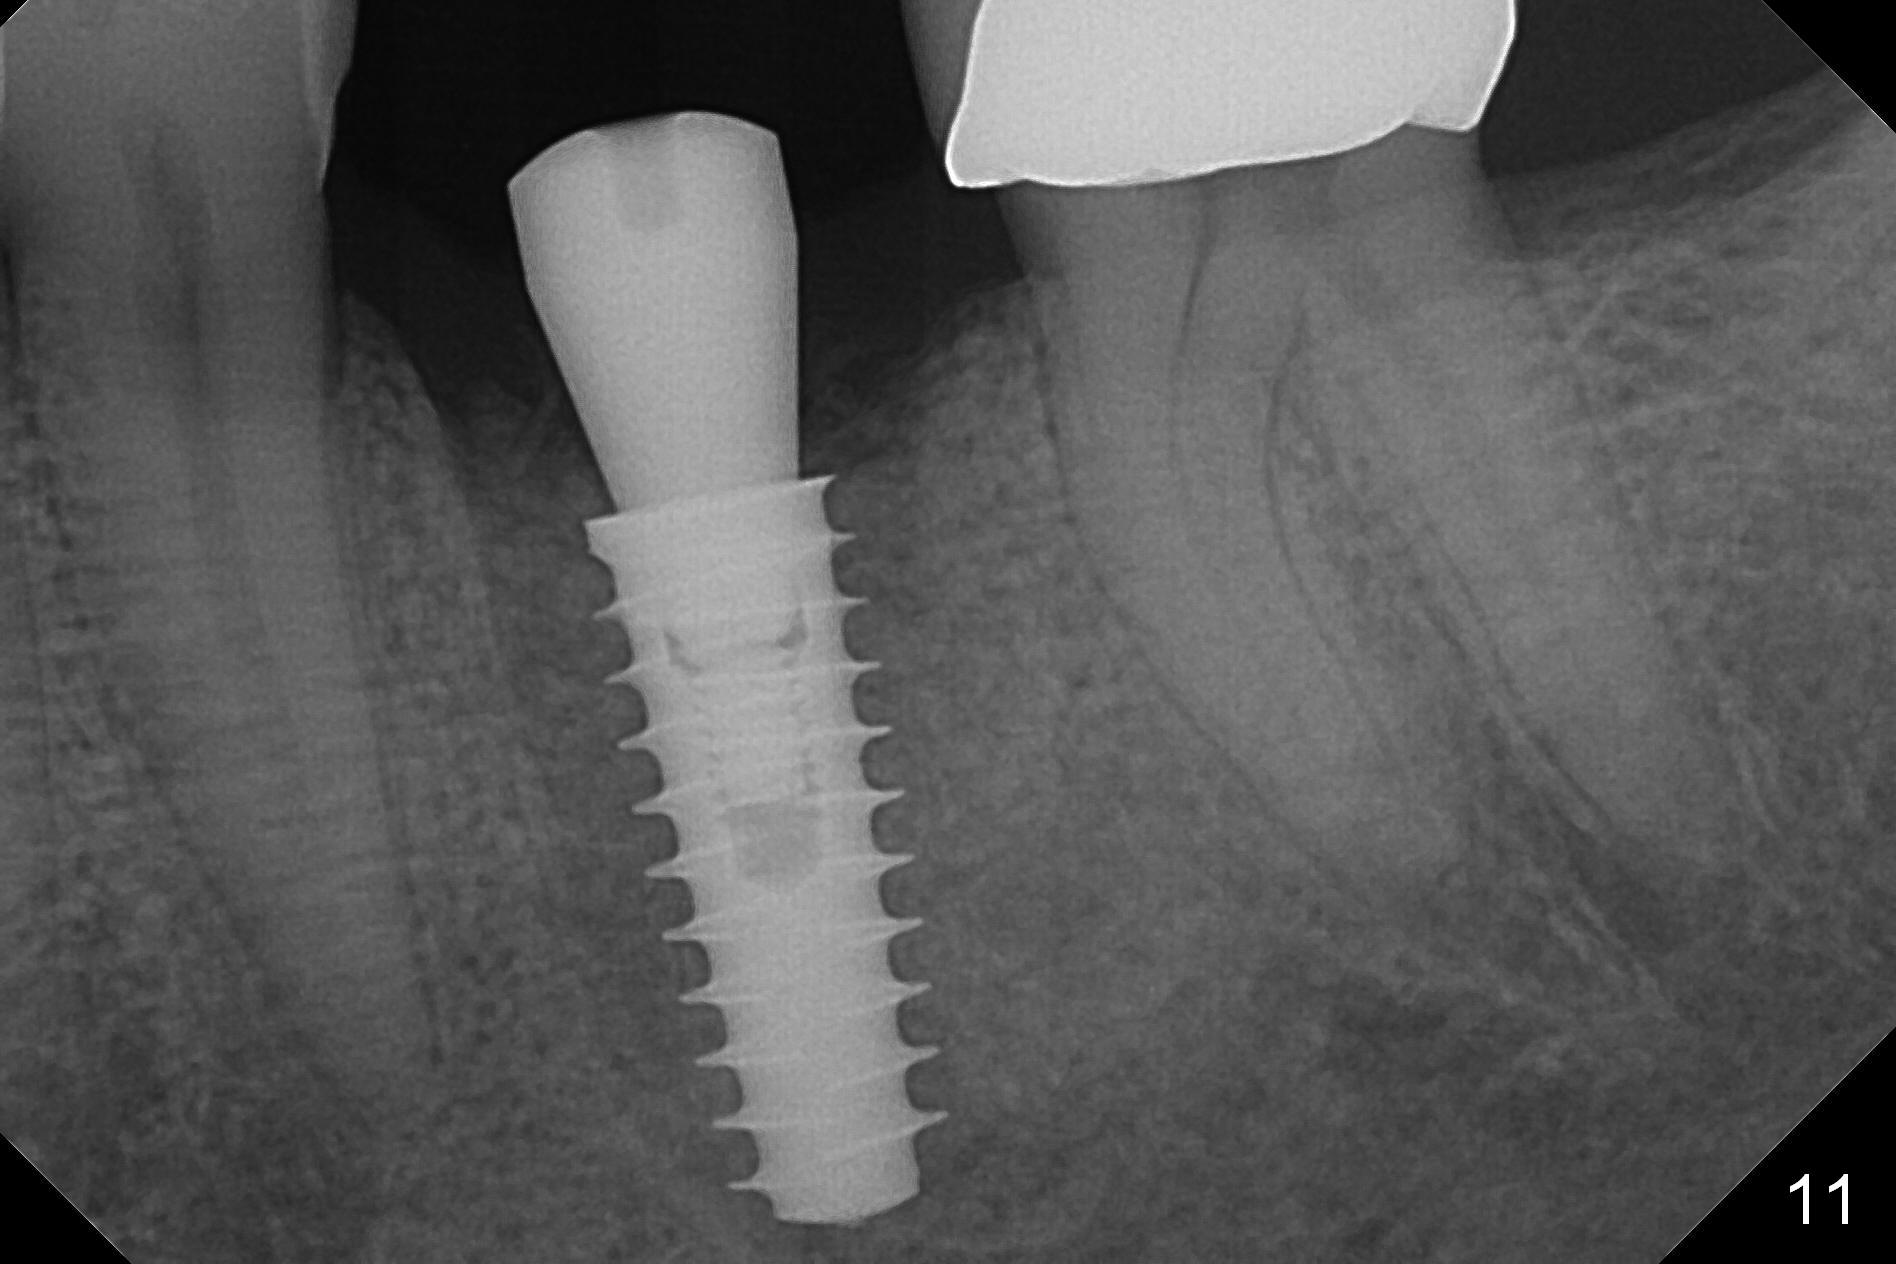

The tooth #19 is easy to get loose, but it cannot be luxated.  After sectioning and extraction (Clindamycin), the septum is found to be thin (Fig.4).  A surgical fissure bur is used to initiate osteotomy, followed by 1.6 mm pilot drill.  It is difficult to use Marking bur (wobbling over the basically pointed septum).  It is impossible to use 4.3 mm Magic Drill (MD, one drill system), since it jumps.  The smallest MD has to be used (2.8 mm).  When the next drill (3.3 mm) is being used for 13 mm with stopper (Fig.5), the patient experiences transient pain.  The depth is suggested from the design in Fig.2.  The thin septum appears not to be a reliable landmark.  When block anesthesia is administered, the initial depth should be shortened.  The drill appears to be close to the Inferior Alveolar Canal (Fig.5).  Then the depth changes to 11 mm with the following drills (3.8 and 4.3).  The mesial and distal walls of the septum are gradually perforated.  A 5x9 mm dummy implant is placed only after using 4.8 mm drill (Fig.6).  The implant appears to be short.  When a longer implant is placed (5x11 mm), it does not easily enter the osteotomy, either sliding into the mesial or distal socket with the implant separating from the implant driver.  It appears that a premount implant is appropriate in this situation.  When the 5x11 mm implant is finally seated with stability, it is 6 mm apical to the gingival margin.  The longest cuff of IBS abutment is 4 mm.  A longer implant is needed (Fig.7, 5x13 mm).  Placement is not easy as mentioned above.  Insertion torque is <20 Ncm when the patient experience a little discomfort.  A 6.5x4(4) mm pair abutment is placed (A), apparently proper for restoration.  Allograft is placed (Fig.8 *) prior to immediate provisional.  The patient complains of bad smell from the site 24 days postop.  When the provisional is removed, the abutment is found to be mobile.  When the latter is removed with local anesthesia, bone graft granules are attached to the socket above the lightly mobile implant (Fig.9).  In fact the latter appears to be stable after a few turns by finger.  A healing screw is placed; the socket is closed with collagen plug and 4-0 Chromic gut sutures (Fig.10).  It appears that a larger implant should have been used to achieve higher torque.  Two months later (3 months postop), the coronal end of the implant is partially exposed.  A 5x4 mm healing abutment is placed.  It appears that the implant is stable.  The implant appears to have osteointegrated 4 months postop (Fig.11).  Impression is taken.